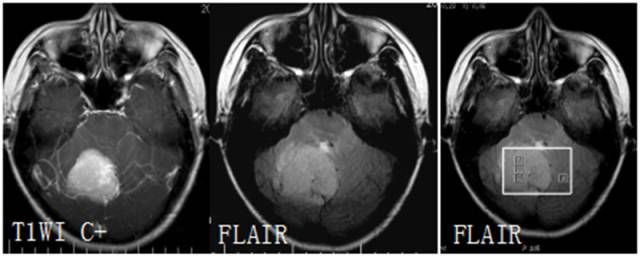

TIWI C 显示病灶呈实质性增强,FLAIR呈高信号,边缘见血管伸入。MRS 病灶内波谱显示Cho峰明显升高,无NAA峰, 出现GHS、Gly峰,并见到Lip峰。结合常规MRI所见,以及 Lip峰不高和瘤周(体素4)浸润不明显,提示含脂肪化生细胞较多的良性脑膜瘤可能为大,但恶性脑膜瘤不能除外。病理图片显示泡沫细胞,可能为出现Lip峰的原因。